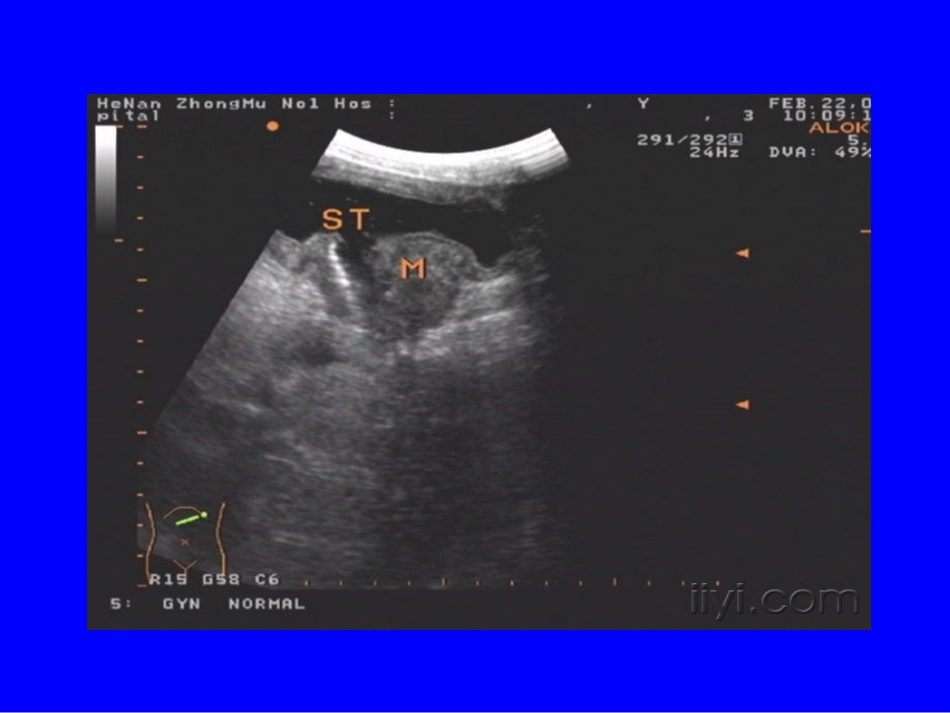

胃癌的超声诊断•胃壁增厚或为肿块状•蠕动波减弱或消失•病变处内腔变窄,内膜不光滑,中心区位置偏移。•幽门狭窄时胃腔扩张•可见血流信号充盈胃癌的超声表现•可分为三型:肿块型溃疡型弥漫浸润型•胃壁分为五层结构:粘膜层粘膜下层粘膜肌层肌层浆膜层肠癌超声表现•肠壁不规则增厚,管腔中心强回声变窄、偏移呈假肾征,肠壁僵硬、蠕动消失。•可表现为单纯性弱回声肿块•可伴有肝转移直肠癌肠套叠超声表现•纵切:套筒征•横切:同心圆征•CDFI:肠系膜血流明显减少或消失肠梗阻超声表现•管腔扩张,小肠内径超过3cm,呈“琴键征”,机械性肠梗阻内容物往返运动频繁,麻痹性肠梗阻,肠蠕动减弱或消失。急性阑尾炎超声表现•单纯性阑尾炎•化脓性阑尾炎•坏疽性阑尾炎•阑尾周围脓肿